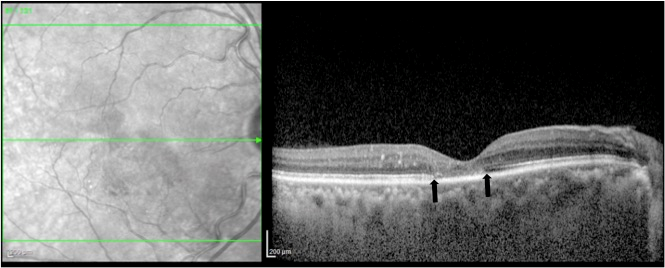

A 60-year old man reported with diminution of vision in the right eye since three months. He had a history of diabetes mellitus and hypertension since 3 years, both well controlled with oral medications. The best corrected visual acuity was 20/80 (+2.5 DS –0.75 DC 80°) in the right eye and 20/20 (+2.25 DS –0.75 DC 75°) in the left eye. The anterior segment was unremarkable in both eyes. Fundoscopy of the right eye showed edema with hard exudates over the macula (Figure 1a [Fig. 1]). The macula of the left eye showed retinal pigment epithelial changes (Figure 1b [Fig. 1]). The peripheral retina did not show any diabetic or hypertensive changes. Spectral domain optical coherence tomography (Heidelberg Engineering Germany) of the right eye revealed cystic changes with thickening of the fovea, hyperreflective dots corresponding to the hard exudates, and attenuation of the ellipsoid zone in the central and temporal parafoveal area (Figure 1c [Fig. 1]). In the left eye, spectral domain optical coherence tomography showed a central hyporeflective space in the outer retina with loss of the ellipsoid zone (Figure 1d [Fig. 1]). Central foveal thickness was 519 µm in the right and 203 µm in the left eye.

Figure 1: Color fundus photo and spectral domain optical coherence tomography of the right and the left eye.

Colour fundus photo showing macular edema with hard exudates in the right eye (a), microaneurysms, RPE changes and a dull foveal reflex in the left eye (b). Horizontal spectral domain optical coherence tomography scan through the fovea revealed cystic changes with thickening of the fovea, hyperreflective dots corresponding to the hard exudates, and attenuation of the ellipsoid zone in the central and temporal parafoveal area of the right eye (c). In the left eye, spectral domain optical coherence tomography showed a central hyporeflective space in the outer retina with loss of the ellipsoid zone (d).

The right eye was treated with intravitreal Ranibizumab (0.5 mg in 0.05 ml). Four weeks post injection, macular thickness reduced to 144 µm and cystic changes disappeared on spectral domain optical coherence tomography. In addition, attenuation of the ellipsoid zone was seen (Figure 4 [Fig. 4]). Vision remained stable.

Figure 4: Horizontal spectral domain optical coherence tomography image through the fovea of the right eye one month after Ranibizumab therapy shows reduction of the central foveal thickness and complete resolution of the cystoid changes. Few hyperreflective dots corresponding to hard exudates are still seen and central loss of ellipsoid zone is seen centrally (between open arrows).